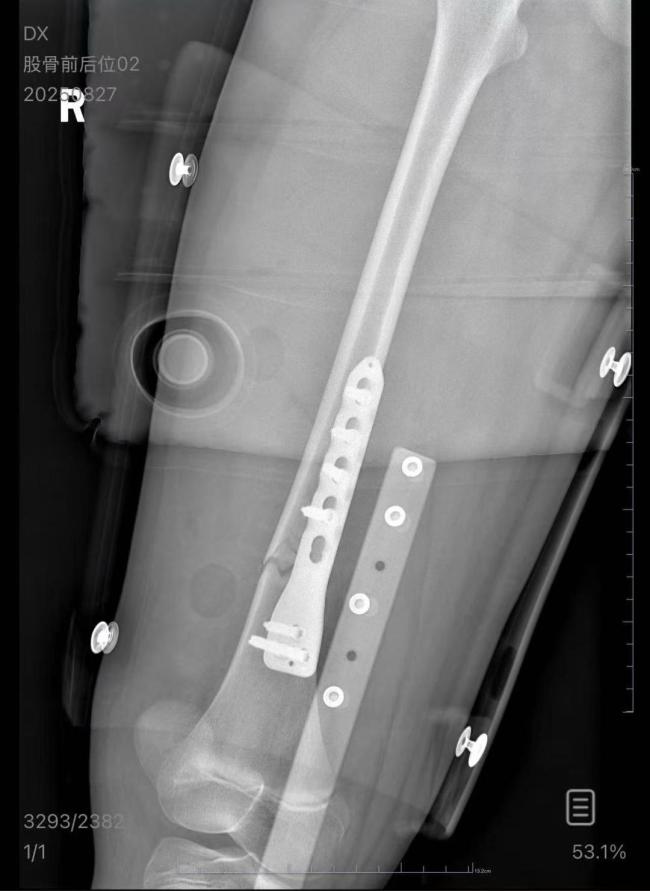

根据男乘客的说法,火车快到无锡站时,他准备下车,从上铺下来后想起还有一副眼镜忘在了铺位上,于是又爬回床铺。这时车晃动了一下,他的手没抓稳,跌下来砸到了女孩。医院诊断结果显示,朱女士的女儿右股骨骨折,需要住院进一步治疗。

朱女士称,女儿爱好游泳,事发前腿部没有受过伤。如今,女儿吃饭、上厕所、学习都只能平躺在床上,情绪低沉。后续的康复治疗是一个漫长的过程,不确定是否会有后遗症。朱女士表示,她知道男乘客不是有意的,并非不能谅解对方,但对方既不接电话也不回微信,这让她很生气。目前,她准备通过法律途径维权。